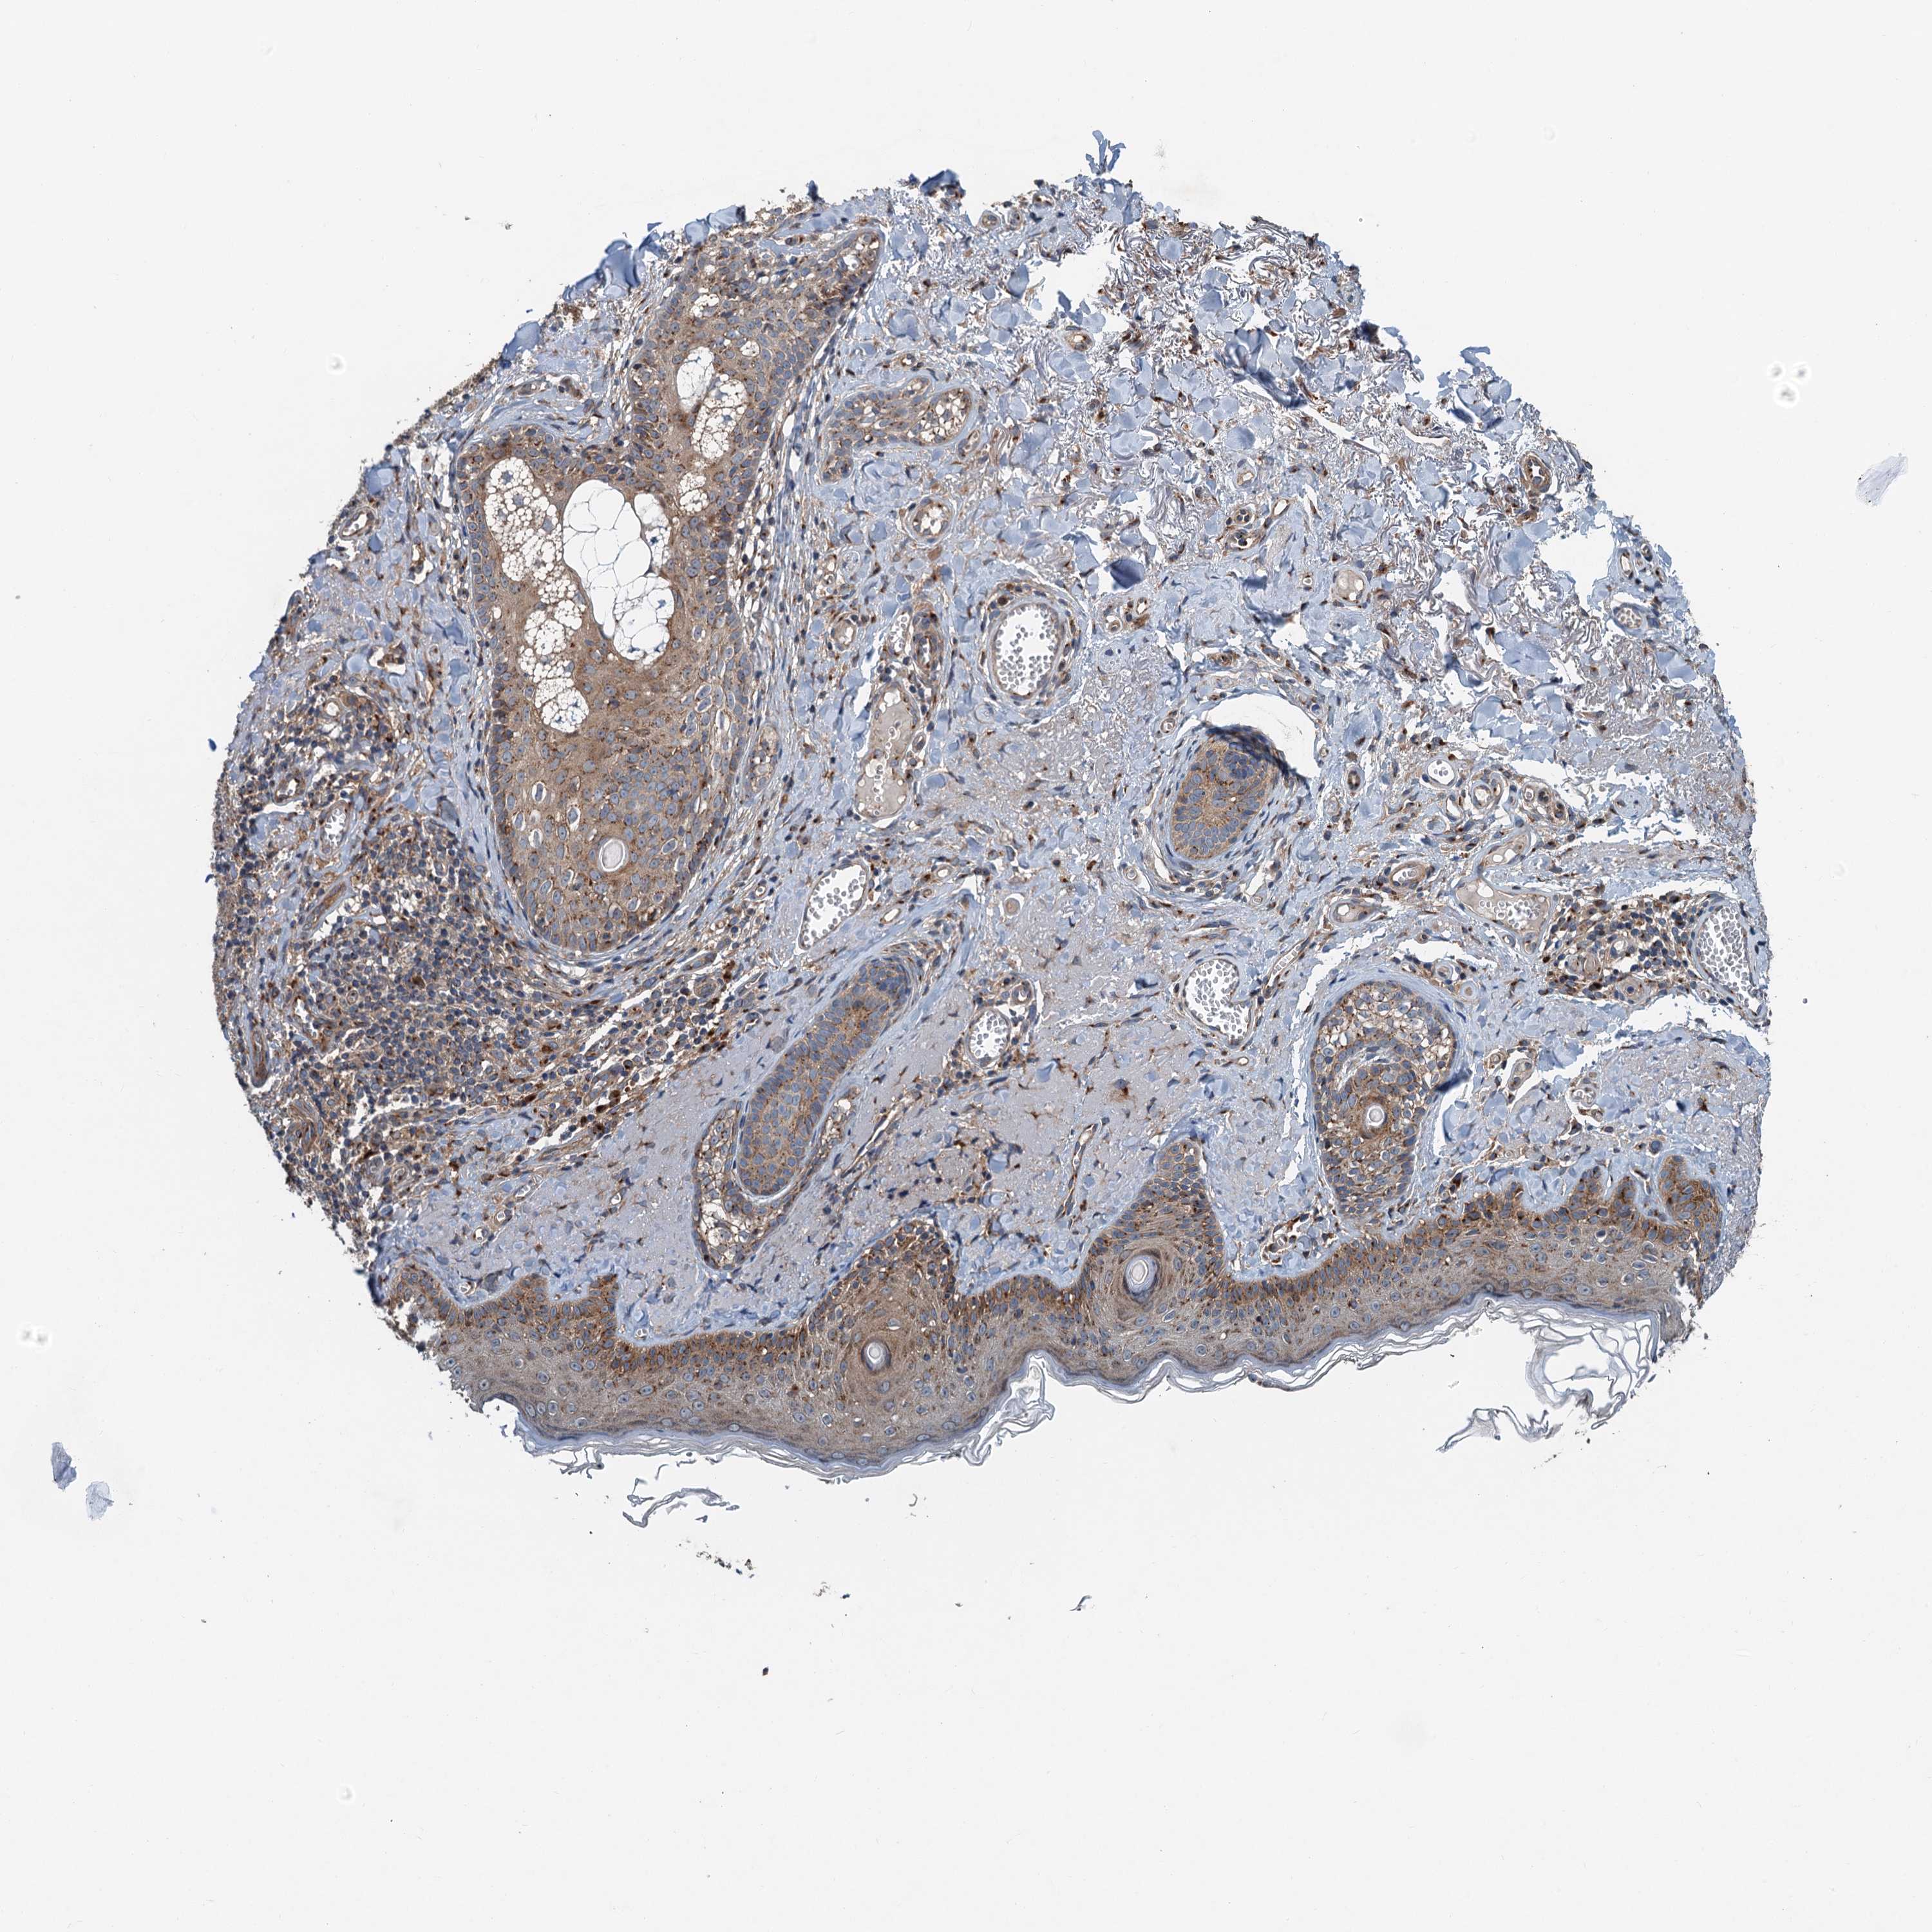

Basal cell and squamous cell cancer

SKIN CANCER - Protein expressioni

A mouse-over function shows sample information and annotation data. Click on an image to view it in a full screen mode. Samples can be filtered based on level of antibody staining by selecting one or several of the following categories: high, medium, low and not detected. The assay and annotation is described here.

Antibody stainingi

Antibody staining in the annotated cell types in the current human tissue is reported as not detected, low, medium, or high, based on conventional immunohistochemistry profiling in selected tissues. This score is based on the combination of the staining intensity and fraction of stained cells.

Each image is clickable and will lead to virtual microscopy that enables deeper exploration of all samples and also displays staining intensity scores, fraction scores and subcellular localization as well as patient and tissue information for each sample.

Antibody HPA040353

Staining

Low

Intensity

Weak

Quantity

75%-25%

Location

Cytoplasmic/membranous,nuclear

Squamous cell carcinoma, metastatic, NOS

Squamous cell carcinoma, NOS